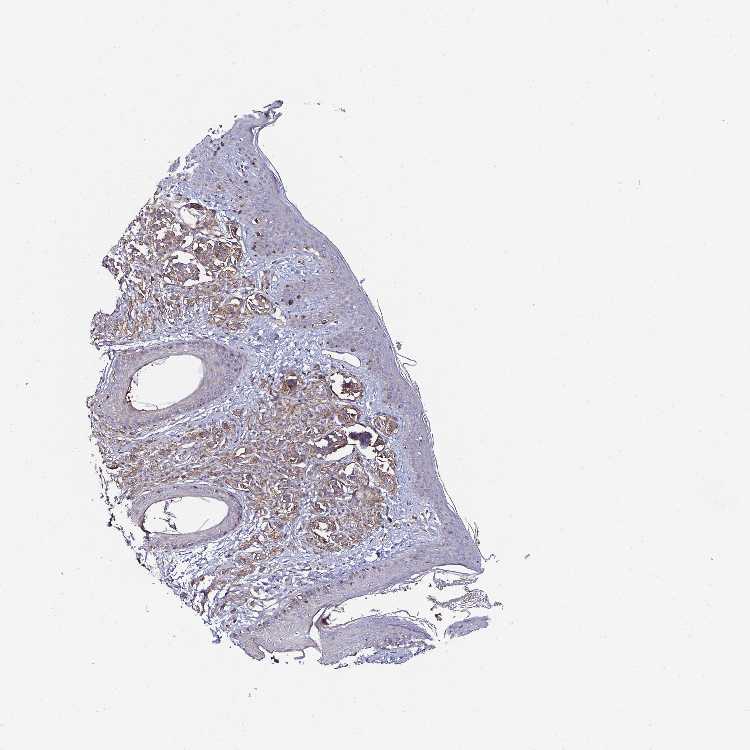

SKIN 1 - Antibody stainingi

Antibody staining in the annotated cell types in the current human tissue is reported as not detected, low, medium, or high, based on conventional immunohistochemistry profiling in selected tissues. This score is based on the combination of the staining intensity and fraction of stained cells.

Each image is clickable and will lead to virtual microscopy that enables deeper exploration of all samples and also displays staining intensity scores, fraction scores and subcellular localization as well as patient and tissue information for each sample.

Antibody HPA054846Antibody CAB021982

Melanocytes Not detectedMedium

SKIN 2 - Antibody stainingi

Epidermal cells MediumNot detected